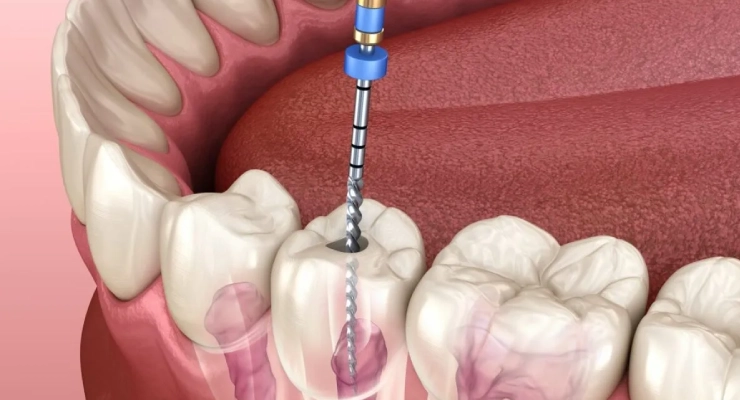

عدم التمييز بين نوعي الألم قد يؤدي إلى تأخير علاج العصب الضروري أو إهمال علاج التهاب اللثة، ما يزيد خطر فقدان الأسنان أو انتشار العدوى إلى العظم المحيط.كما أن فهم الفرق بين ألم اللثة وألم العصب يساعد الطبيب في وضع خطة علاج دقيقة، مثل تنظيف عميق للثة أو علاج جذور الأسنان (سحب العصب)،

ألم العصب هو نوع خاص من الألم ينتج عن تهيّج أو التهاب أو تلف في العصب المسؤول عن الإحساس في منطقة معينة، مثل عصب السن أو عصب الفك. يختلف ألم العصب عن ألم اللثة العادي، فهو يكون عادة حادًا، يشبه الصدمة الكهربائية أو الوخز أو الحرق، وقد يمتد من السن إلى الفك أو الأذن أو الرأس. في كثير من الحالات لا يظهر انتفاخ واضح في اللثة، لكن يشعر المريض بألم مفاجئ يزداد مع تناول الأطعمة الساخنة أو الباردة أو عند الضغط على السن.

يساعد التمييز بين ألم العصب وألم اللثة على اختيار العلاج المناسب، مثل علاج العصب (سحب العصب) أو تنظيف اللثة وعلاج الالتهابات السطحية. فهم طبيعة ألم العصب في الأسنان واللثة يمكّن المريض من طلب المساعدة الطبية في الوقت المناسب قبل تفاقم المشكلة وحدوث مضاعفات أكثر خطورة.

ألم العصب في الأسنان يحدث غالبًا نتيجة وصول التسوس العميق إلى لب السن، حيث يوجد العصب والأوعية الدموية المسؤولة عن الإحساس. عندما تهمل معالجة تسوس الأسنان أو كسر السن، يمكن أن تلتهب أعصاب الأسنان وتسبب ألمًا حادًا ومستمراً يختلف تمامًا عن ألم اللثة السطحي. كما قد ينشأ ألم العصب بسبب صدمة قوية على الأسنان، مثل السقوط أو الارتطام، مما يؤدي إلى تلف العصب الداخلي حتى لو بدا السن سليمًا من الخارج.

أعراض تدل على أن الألم من العصب

عندما يكون الألم من عصب السن، غالبًا ما يكون حادًا، نابضًا، ويزداد سوءًا خاصة في الليل أو عند الاستلقاء. من العلامات المميزة لألم العصب أن الألم يستمر حتى بعد إزالة المسبب، مثل استمرار الألم بعد إبعاد المشروب البارد أو الساخن، بعكس ألم اللثة الذي يخف عادة بزوال المهيّج. كما قد ينتشر ألم العصب إلى الفك، الأذن أو الرأس، فيشعر المريض بصعوبة في تحديد السن المصاب بدقة. قد يصاحب ألم عصب الأسنان تورم في الوجه أو ظهور خراج، مع صعوبة في المضغ على الجهة المصابة. أحيانًا يشعر المريض بحساسية شديدة للحرارة والبرودة، وألم مفاجئ بدون سبب واضح، وهي علامات قوية على أن المشكلة من العصب وليس من اللثة. التعرف على هذه الأعراض يساعد على التمييز بين ألم اللثة وألم العصب، ما يسهّل اتخاذ القرار بمراجعة طبيب الأسنان فورًا للعلاج قبل تفاقم الالتهاب.

يعتمد طبيب الأسنان على مجموعة من الخطوات الدقيقة لتحديد ما إذا كان الألم ناتجًا عن التهاب اللثة أم عن ألم العصب داخل السن. يبدأ أولًا بأخذ التاريخ المرضي بالتفصيل، مثل مدة الألم، وحدّته، وهل يزداد ليلًا أو مع تناول المشروبات الباردة أو الساخنة، وهي علامات مهمة للتمييز بين ألم اللثة وألم العصب. بعد ذلك يقوم بفحص اللثة سريريًا للبحث عن احمرار، تورم، نزيف عند اللمس، أو وجود جيوب لثوية، وهي مؤشرات قوية على التهاب اللثة.

كما يستخدم أدوات خاصة للضغط على السن واللثة، ويجري اختبارات حرارية وكهربائية لقياس استجابة العصب، لأن استمرار الألم بعد زوال المؤثر غالبًا ما يشير إلى التهاب عصب السن. في بعض الحالات، يلجأ الطبيب إلى أشعة سينية رقمية عالية الدقة للكشف عن التسوس العميق، أو التهابات حول جذر السن، أو تآكل العظم الداعم، مما يساعد على تأكيد ما إذا كان مصدر الألم من العصب السني أو من أنسجة اللثة المحيطة. هذا التشخيص الدقيق هو الأساس لاختيار خطة علاج مناسبة، سواء لعلاج التهاب اللثة أو علاج عصب السن، وتخفيف الألم بطريقة فعّالة وآمنة.